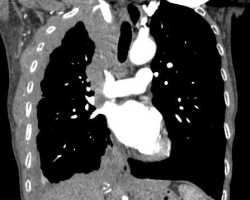

Thrombose de l’aorte